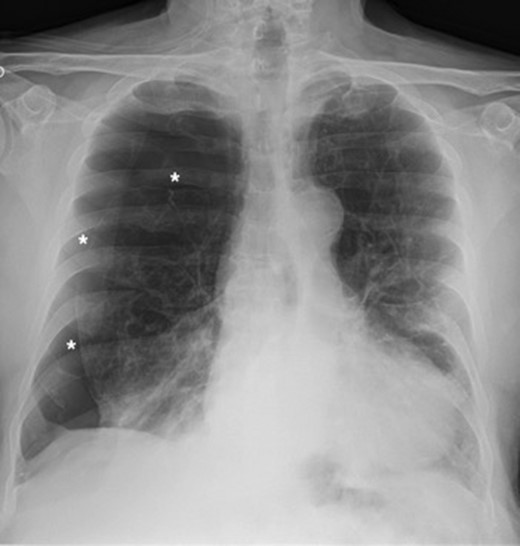

A 73-year-old male patient with a clinical history of COPD, lung emphysema and a 30-year smoking history was admitted to the ED due to a 24-h clinical picture of dyspnea immediately following a sudden bout of dry coughing. Physical examination showed a dyspneic patient, tachypnea of 25 rpm, heart rate of 85 bpm and blood Pressure of 135/75 mmHg along with central cyanosis. Chest exam showed a hyper-resonant right hemithorax along with reduced breath sounds. Initial chest X-ray revealed a large right-sided pneumothorax (Fig. 1). A right chest tube was placed in the ED. Emergency echocardiogram had no significant findings and spirometry showed suspected patterns of obstruction. Following patient stabilization, a high-resolution chest computed tomography (HRCT) was performed revealing extensive pan lobar emphysema throughout both lungs, para septal emphysema in both the anterior upper lobes and herniation of a left lung bullae through the anterior mediastinal pleura along with a right-sided pneumothorax with the chest tube in place with persistent air space (Fig. 2). The patient was taken to surgery where a right video-assisted thoracoscopic (VATS) approach showed severe lung emphysema and a contralateral herniated left lung bulla through the mediastinal pleura anterior to the pericardium (Fig. 3). Right pleurodesis was performed using Talc and a left posterior thoracoscopy showed a severe emphysematous left lung with a lingular herniated bulla to the right hemithorax through an anterior mediastinal pleural defect along with pleural adhesions (Figs 4 and 5). Thoracoscopic hernia reduction was performed along with bullectomy using 60 mm mechanical sutures (Fig. 6). Chest tubes were removed on POD 3 (right) and POD 4 (left). The patient had significant respiratory improvement and was discharged on POD 5.

Thoracoscopic view from left side of transmediasinal hernia of pulmonary bulla after reduction (asterisk).